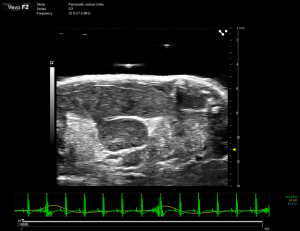

Developed SOP SOP(Standard Operating Procedure) Optical Images EM MR CT EPhys(EEG, MEG) Others Developed SOP SOP(Standard Operating Procedure) Optical Images EM MR CT EPhys(EEG, MEG) Others